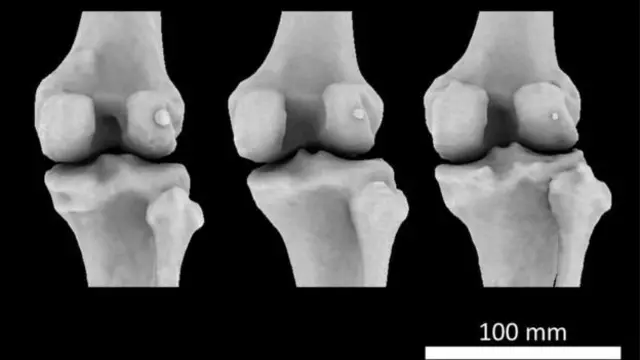

منبع تصویر، IMPERIAL COLLEGE LONDON

در میمونسانان، فابلا میتواند کاری مثل کشکک داشته باشد، زور ماهیچه را بیشتر کند. اما وقتی اجداد میمونها بزرگ جثه و انسان تکامل مییافت بتدریج این استخوان را از دست دادند.

اما اکنون این استخوان برگشته و دردسرساز شده است. کسانی که استئوآرتریت (آرتروز) زانو دارند دو برابر بیشتر ممکن است این استخوان کوچک را در زانو داشته باشند تا کسانی که آرتروز زانو ندارند.